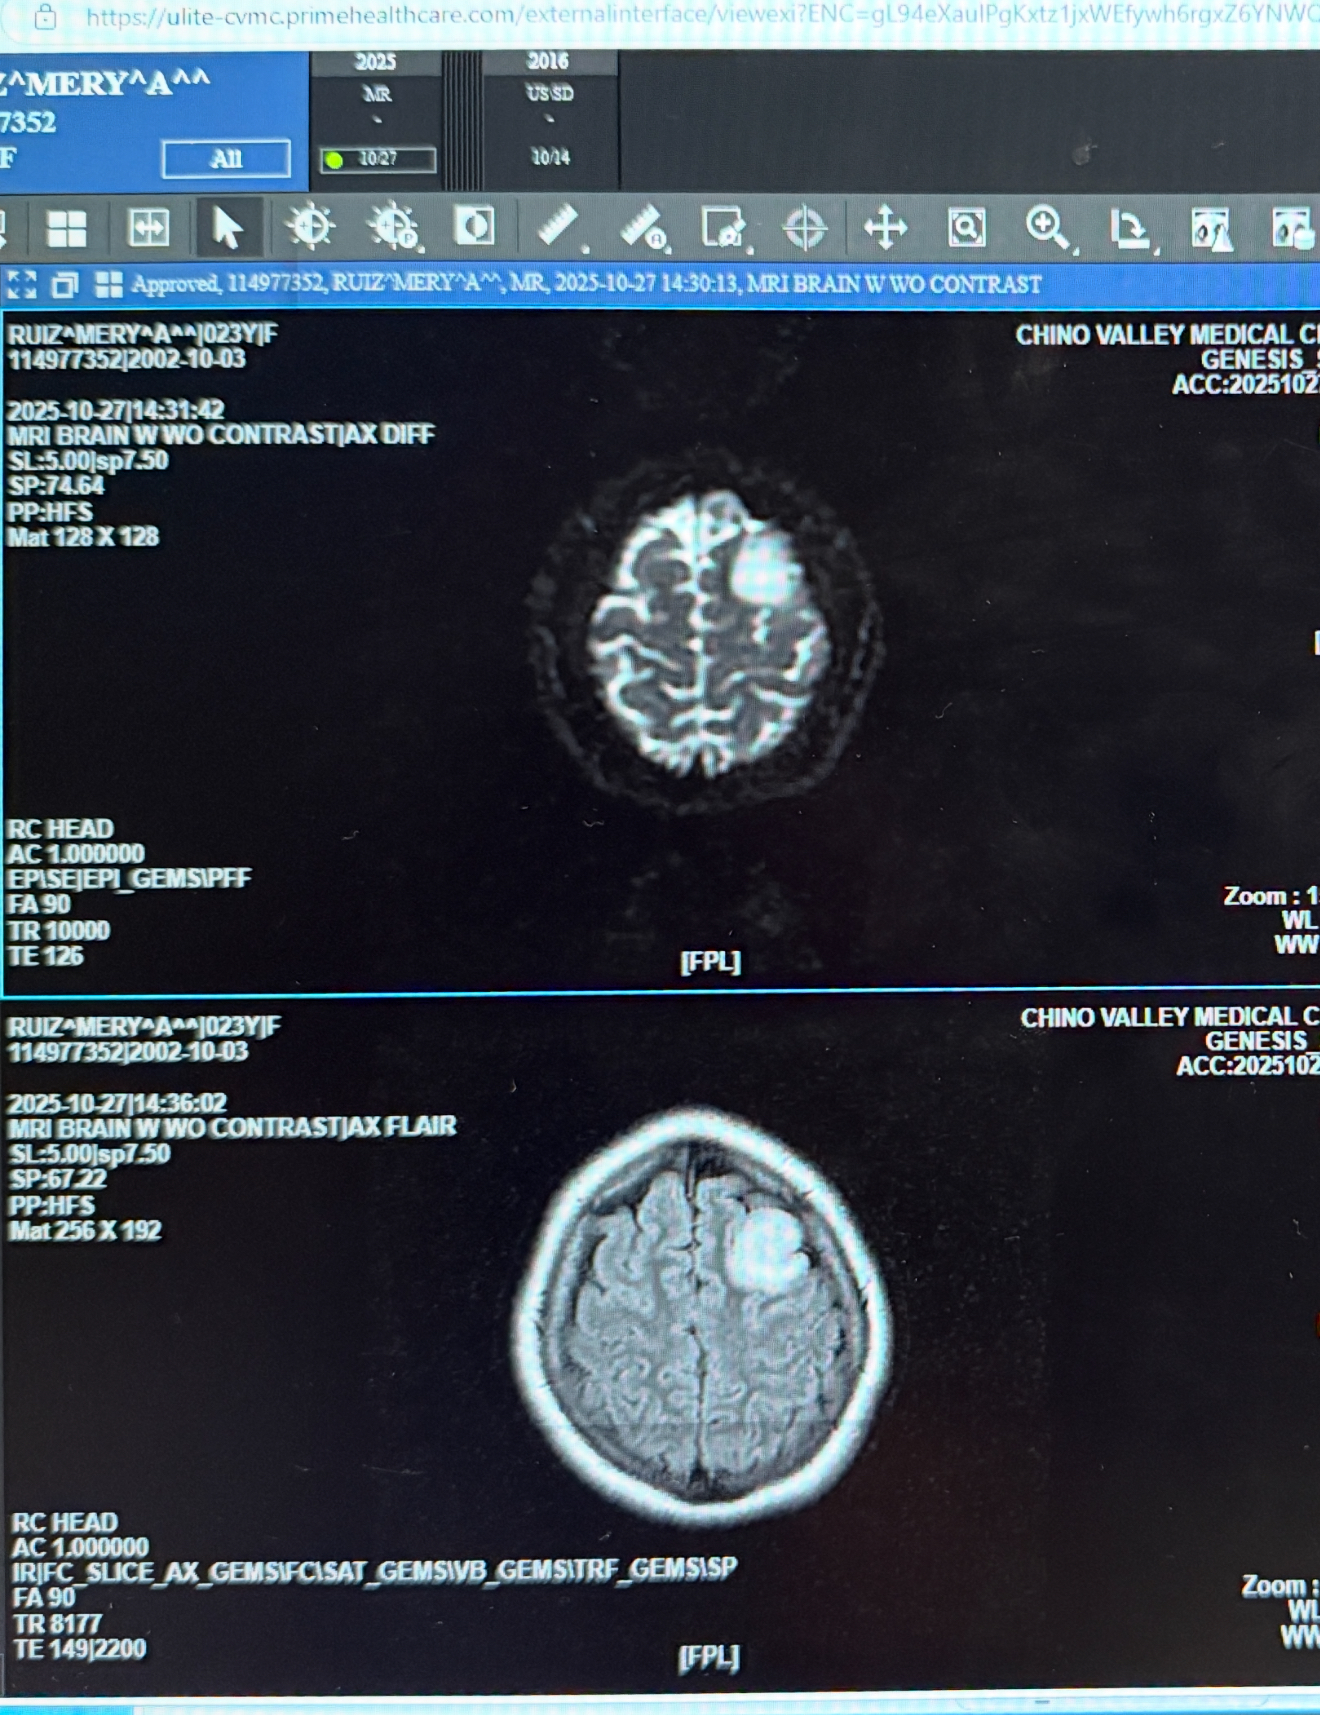

I never imagined I’d be in this position, but I’m reaching out for help during one of the hardest times of my life. Recently, I was hospitalized after suffering a seizure, which led to the discovery of a brain tumor. I’m currently undergoing treatment and recovery, and while I focus on healing, the medical bills and everyday expenses are piling up.